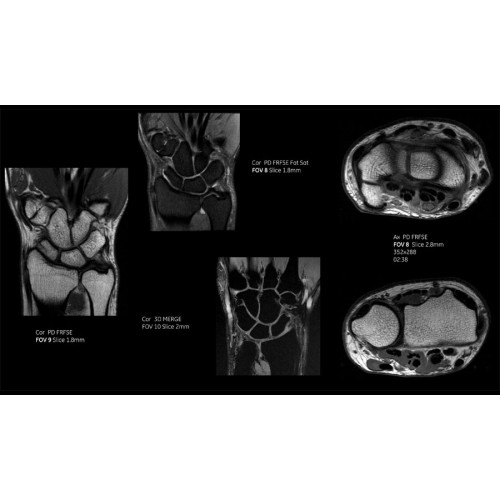

Система SIGNA Pioneer воплощает поразительные достижения в области визуализации. Передовая технология Total Digital Imaging (TDI) позволяет добиться большей четкости изображений и на четверть повысить соотношение сигнал/шум.

• Технология Direct Digital Interface (DDI) использует независимый аналого-цифровой преобразователь для оцифровки сигнала от каждого из 97 радиочастотных каналов, что обеспечивает значительное увеличение качества за счет уменьшения фонового шума.

• Технология Digital Micro Switching (DMS) — это следующее поколение технологий радиочастотных катушек, основанное на замене аналоговых схем блокировки сверхбыстрыми микропереключателями (MEMS), что делает возможным быстрое переключение катушек для дальнейшего расширения возможностей визуализации с нулевым TE.

• Технология Digital Surround Technology (DST) — это новая технология объемной оцифровки данных, объединяющая сигналы от каждого элемента катушки. Прекрасное соотношение сигнал/шум и чувствительность поверхностных катушек в сочетании с превосходной однородностью и высокой проникающей способностью встроенной радиочастотной катушки — все это позволяет создавать качественные изображения не только позвоночника, но и всего тела.